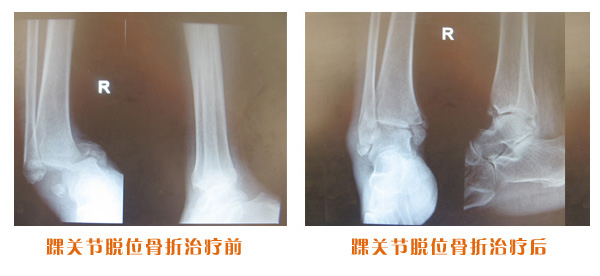

肥城市安駕莊梁氏骨科醫(yī)院是一所以梁氏手法正骨配合膏藥為特色的現(xiàn)代化專科醫(yī)院。

梁氏骨科術(shù)始創(chuàng)于清雍正年間,歷經(jīng)八代,至今已有三百年歷史。據(jù)1929年泰安縣志載“梁瑞圖先生,字增生,號蓮峰,安駕莊人,精岐黃并發(fā)明接骨,凡跌打車凡跌打車軋皮不破而碎骨者......【詳細】 |